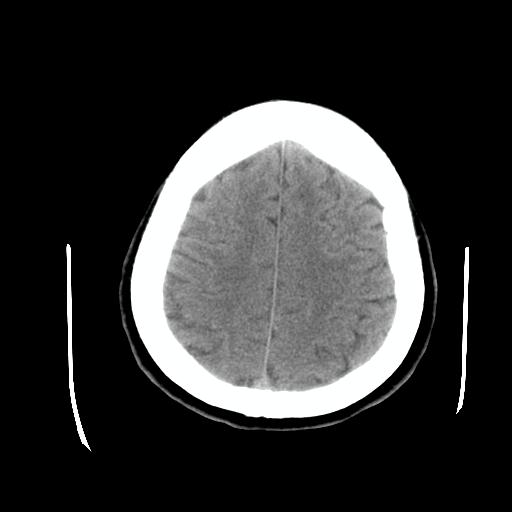

比较下

脉络丛囊肿属神经上皮性囊肿.好发于双侧脉络膜球,通常于影像检查或活检时偶然发现.患者无症状,病灶较小,双侧对称性,脑室膨胀轻.多数病灶在信号上与室管膜囊肿有所不同.在dwi上呈部分高信号,t2 flair上呈不均匀高信号.增强后呈结节状或环形增强

脉络丛囊肿属神经上皮性囊肿.好发于双侧脉络膜球,通常于影像检查或活检时偶然发现.患者无症状,病灶较小,双侧对称性,脑室膨胀轻.多数病灶在信号上与室管膜囊肿有所不同.在dwi上呈部分高信号,t2 flair上呈不均匀高信号.增强后呈结节状或环形增强!支持!